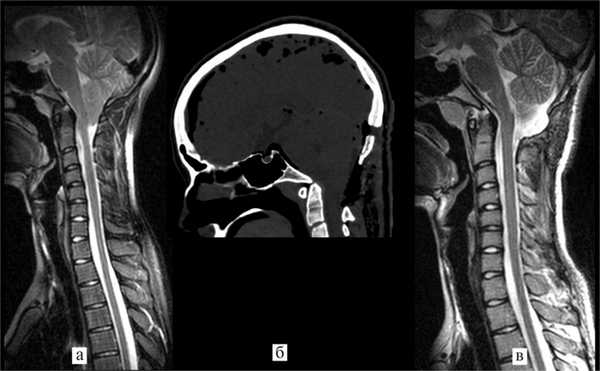

Рис. 1. Данные МРТ и КТ до и после операции. а — МРТ головного мозга до операции: видна клиновидная деформация миндаликов мозжечка и их дислокация в большое затылочное отверстие ниже уровня дужки С1 позвонка; б, в — КТ головного мозга спустя 12 ч после операции: видно, что новое положение костного лоскута (указан желтой стрелкой) позволяет увеличить диаметр большого затылочного отверстия и объем задней черепной ямки; г — МРТ спустя 3 мес после операции: миндалики мозжечка занимают нормальное положение, виден просвет большой затылочной цистерны, нет признаков псевдоменингоцеле.

Послеоперационное течение. Течение послеоперационного периода было гладким, осложнений не отмечено. Компьютерная томография спустя 12 ч после операции подтвердила удовлетворительное положение костного лоскута (см. рис. 1, б, в. и рис. 3). Пациентка выписана домой спустя 36 ч после операции и вернулась к занятиям в школе через неделю после нее. При контрольном осмотре спустя 3 мес после операции она отметила полный регресс головной боли, боли в шейно-затылочной области, приступы судорог после операции также не повторялись. МРТ головного мозга через 3 мес после операции (см. рис. 1, г) выявила нормальное положение миндаликов мозжечка, появление просвета большой затылочной цистерны, признаков псевдоменингоцеле не было.